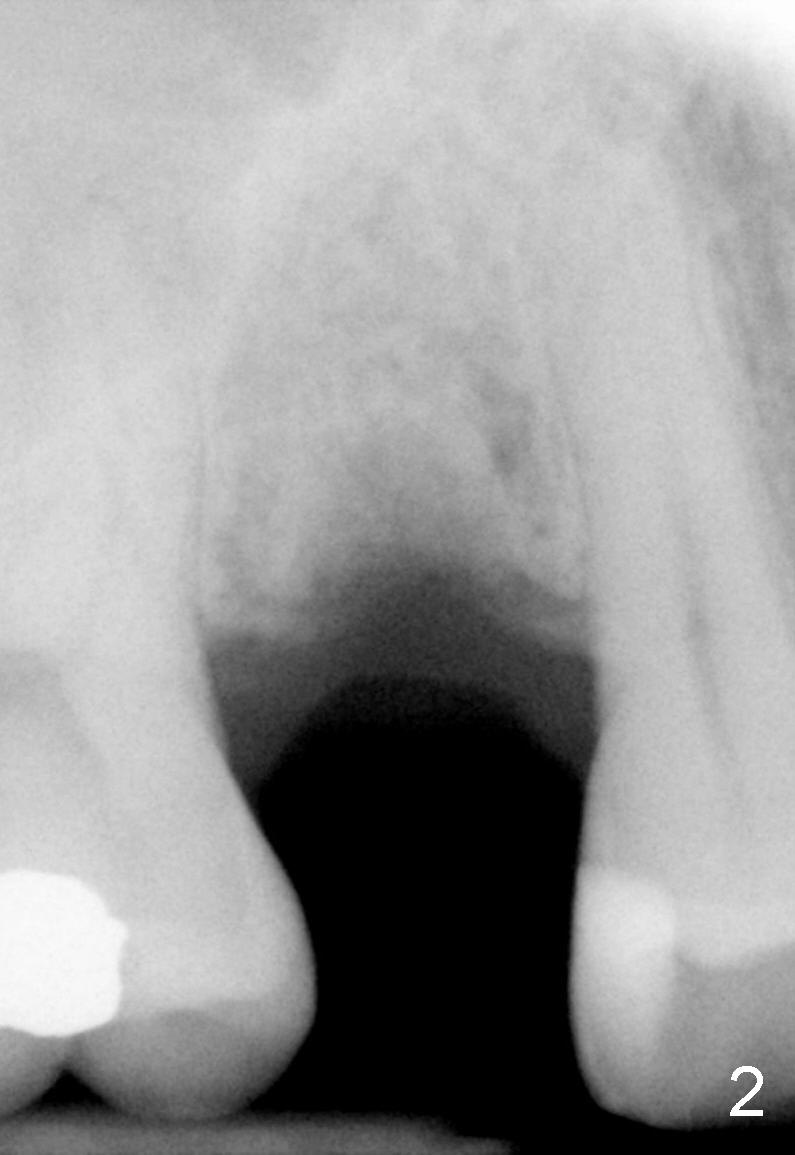

The tooth #4 was removed from a 41-year-old man (Fig.1). Fig.2 was taken 1 year and 7 months post extraction. Osteotomes (Fig.3,4) were used to create osteotomy (7 yr 9 m post ext). A 4x14 mm implant was placed below the sinus floor with insertion torque > 60 Ncm (Fig.5). The surgery was flapless (Fig.6). No antibiotic was taken pre- and post-op. The implant was found to be tender and loose. It was removed without bone graft.